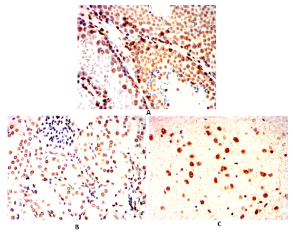

IHC    1/100 - 1/500